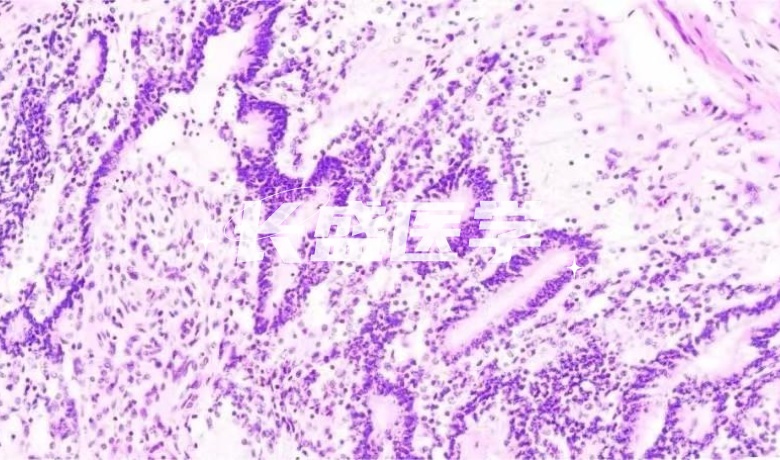

HE染色

HE染色法,又称为苏木精-伊红双染法,是生物领域中最基础且最常用的染色方法之一。该方法可使细胞和组织的核和细胞质可视化,为观察病理形态提供了重要帮助。

苏木精-伊红染色法,通常被简称为HE染色法,是一种广泛使用的染色方法。其中,苏木精(hematoxylin)是一种阳离子染料,主要作用在于将细胞核内的嗜碱性物质染成蓝紫色。而伊红(eosin)则是一种阴离子染料,其作用是将细胞质和胶原纤维等染成粉红色。这种染色方法在生物医学领域中被广泛使用,其结构清晰、准确的染色效果为研究人员提供了重要的参考,同时也被用于临床诊断和教学中。由于其极高的可靠性和实用性,HE染色法已经成为了现代生物染色技术中的重要方法之一。